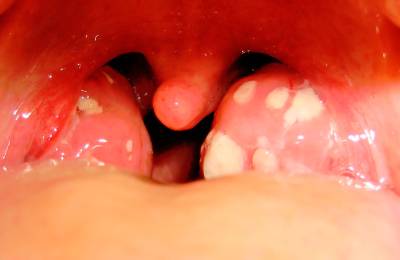

При гнойной ангине поражаются верхние дыхательные пути. По природе болезнь является инфекционной. Воспалительный процесс происходит на нёбе и на миндалинах. На гортанной ткани появляется покраснение и отек. Миндалины покрываются небольшими налетами – гнойниками.

- покрытие миндалин гнойниками;

Гнойная ангина — это инфекционное заболевание, которое вызывает воспаление миндалин и может сопровождаться сильной болью в горле. Люди часто отмечают, что одним из первых симптомов является резкая боль при глотании, а также повышение температуры до 39°C и выше. Нередко наблюдаются головные боли, слабость и увеличение лимфатических узлов. Внешний вид миндалин может быть тревожным: они становятся отечными и покрываются белыми или желтоватыми налетами.

Основные симптомы гнойной ангины включают сильную боль в горле, затрудненное глотание, повышение температуры тела, общее недомогание, а также наличие белых или желтых налетов на миндалинах. У некоторых пациентов могут наблюдаться увеличенные лимфатические узлы на шее.